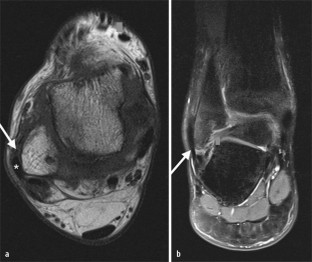

Abb. 1